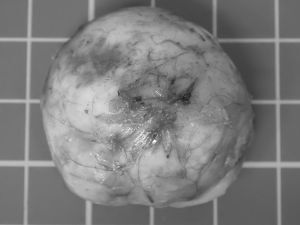

最初は他院でお薬をもらって様子を見ていましたが、腫れはどんどん大きくなり、当院で診察すると頬の下にしっかりとした巨大な腫瘤が触れました。

小さな体に負担がかからないよう慎重に麻酔をかけ、腫瘤を周囲の組織から丁寧に分離して摘出。

病理検査の結果、腫瘤は「組織球肉腫」という腫瘍でした。